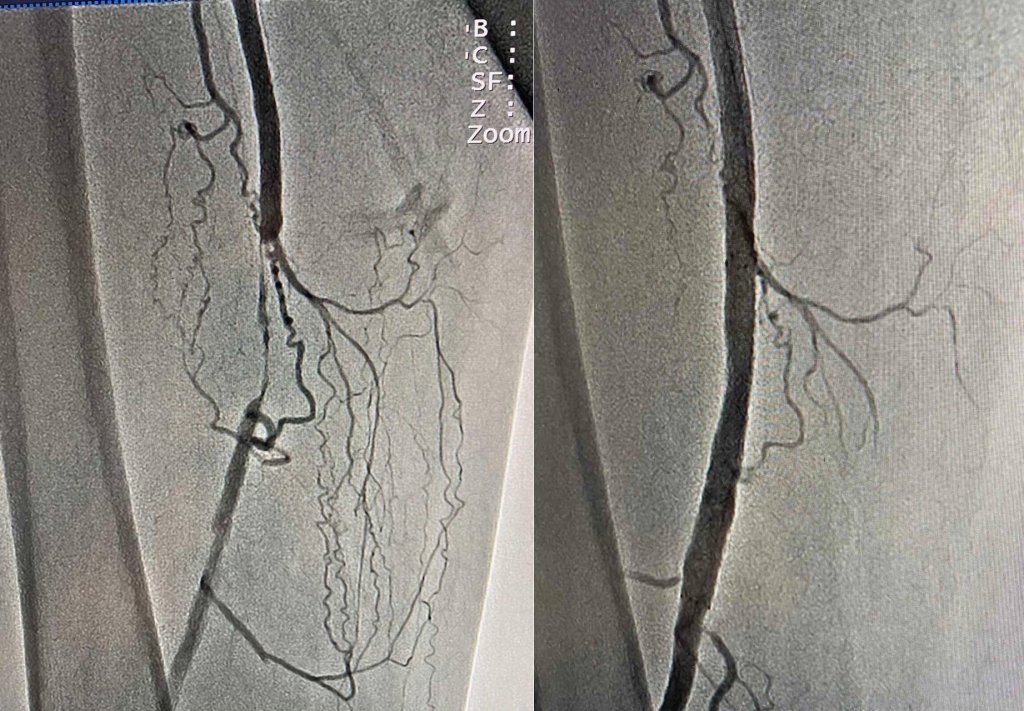

Фахівцями відділення інтервенційної радіології було вирішено провести дослідження судин (ангіографію) ураженої кінцівки, у ході якої виявили порушення кровотоку та повну оклюзія у поверхневій стегновій артерії.

Врятувати ногу чоловіку можна було лише провівши стентування. Команда судинних хірургів на чолі з Олександром Голубом успішно виконала малоінвазивне оперативне втручання з відновлення кровопостачання